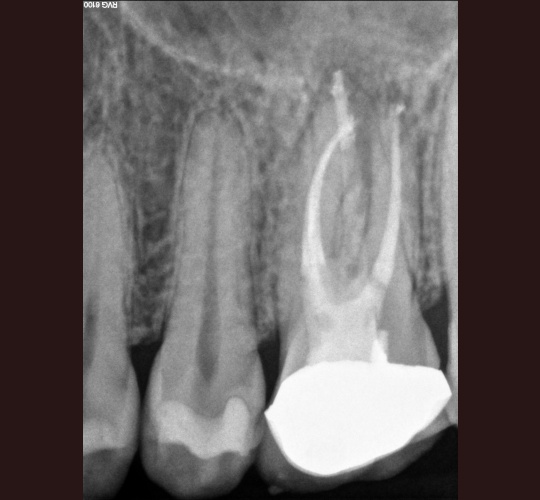

Endodontic Retreatment: Case #5 – Retreatment of initial root canal done 30 years earlier.

Problem 7 mm periodontal pocket on the buccal side with slight pain to biting. His general dentist felt that the tooth may be fractured and referred the patient to determine if an extraction is necessary. During examination we determined that there was a missed DL canal that is challenging to locate. This type of tooth…